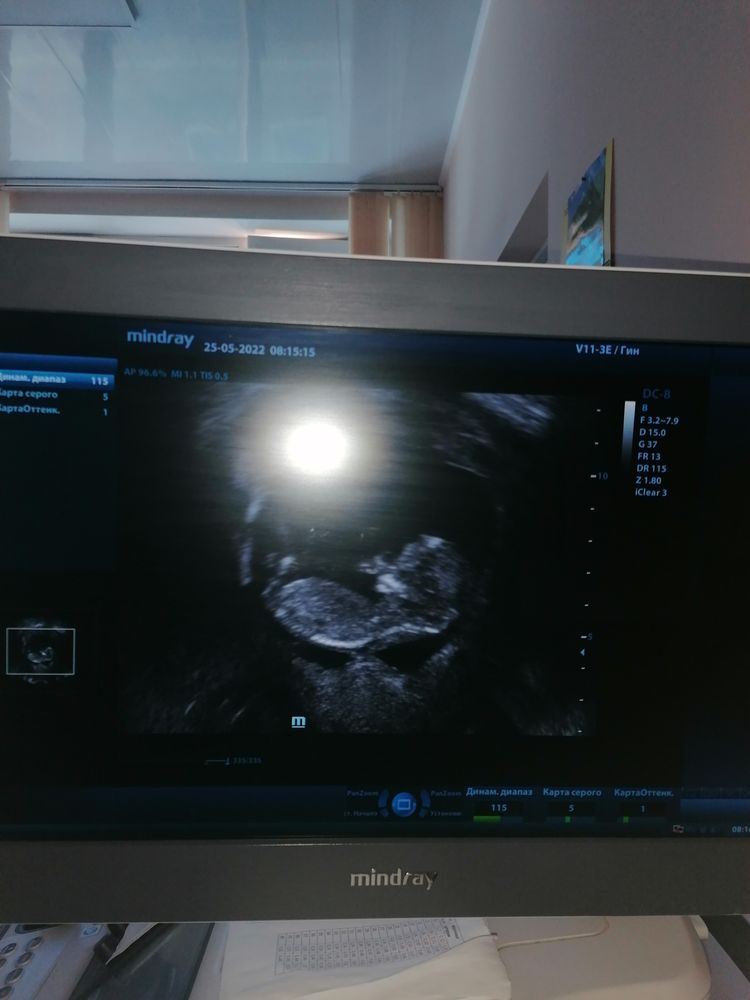

Первый скрининг (25.05.2022), 12 недель + 4 дня

Изображение Елена, спасибо, прикладываю протокол скрининга. По УЗИ патологии нет, надеюсь по крови тоже будет все в норме. Чего и вам желаю

Ирина, спасибо большое за узи, так интересно!!! Все хорошо у Вас, и это видно по узи. Значит и кровь будет с отличным результатом.